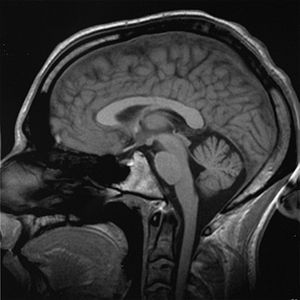

يتكون الدماغ البشري من كرة هلامية رمادية تميل إلى اللون الوردي، ويتميز سطحه بالعديد من النتوءات والأخاديد. ويزن دماغ المولود حديث الولادة أقل من نصف كيلوجرام، وعندما يصل إلى ست سنوات يصبح وزن دماغه 1,4 كجم، وهو أقصى ما يصل إليه في الوزن.

والدماغ یتألف من عشرات الملیارات من الخلایا العصبیة والتي العصبة الواحدة فیه تکون مرتبطا بجموعة کبیرة (أحیانا مع الآلاف) من الأعصاب المجاورة لها. يتألف دماغ الإنسان من عدة أقسام : المخ والمخيخ والبصلة السيسائية.

تشريح الدماغ عند الإنسان

ينقسم الدماغ عند الإنسان إلى ثلاثة أقسام رئيسية: